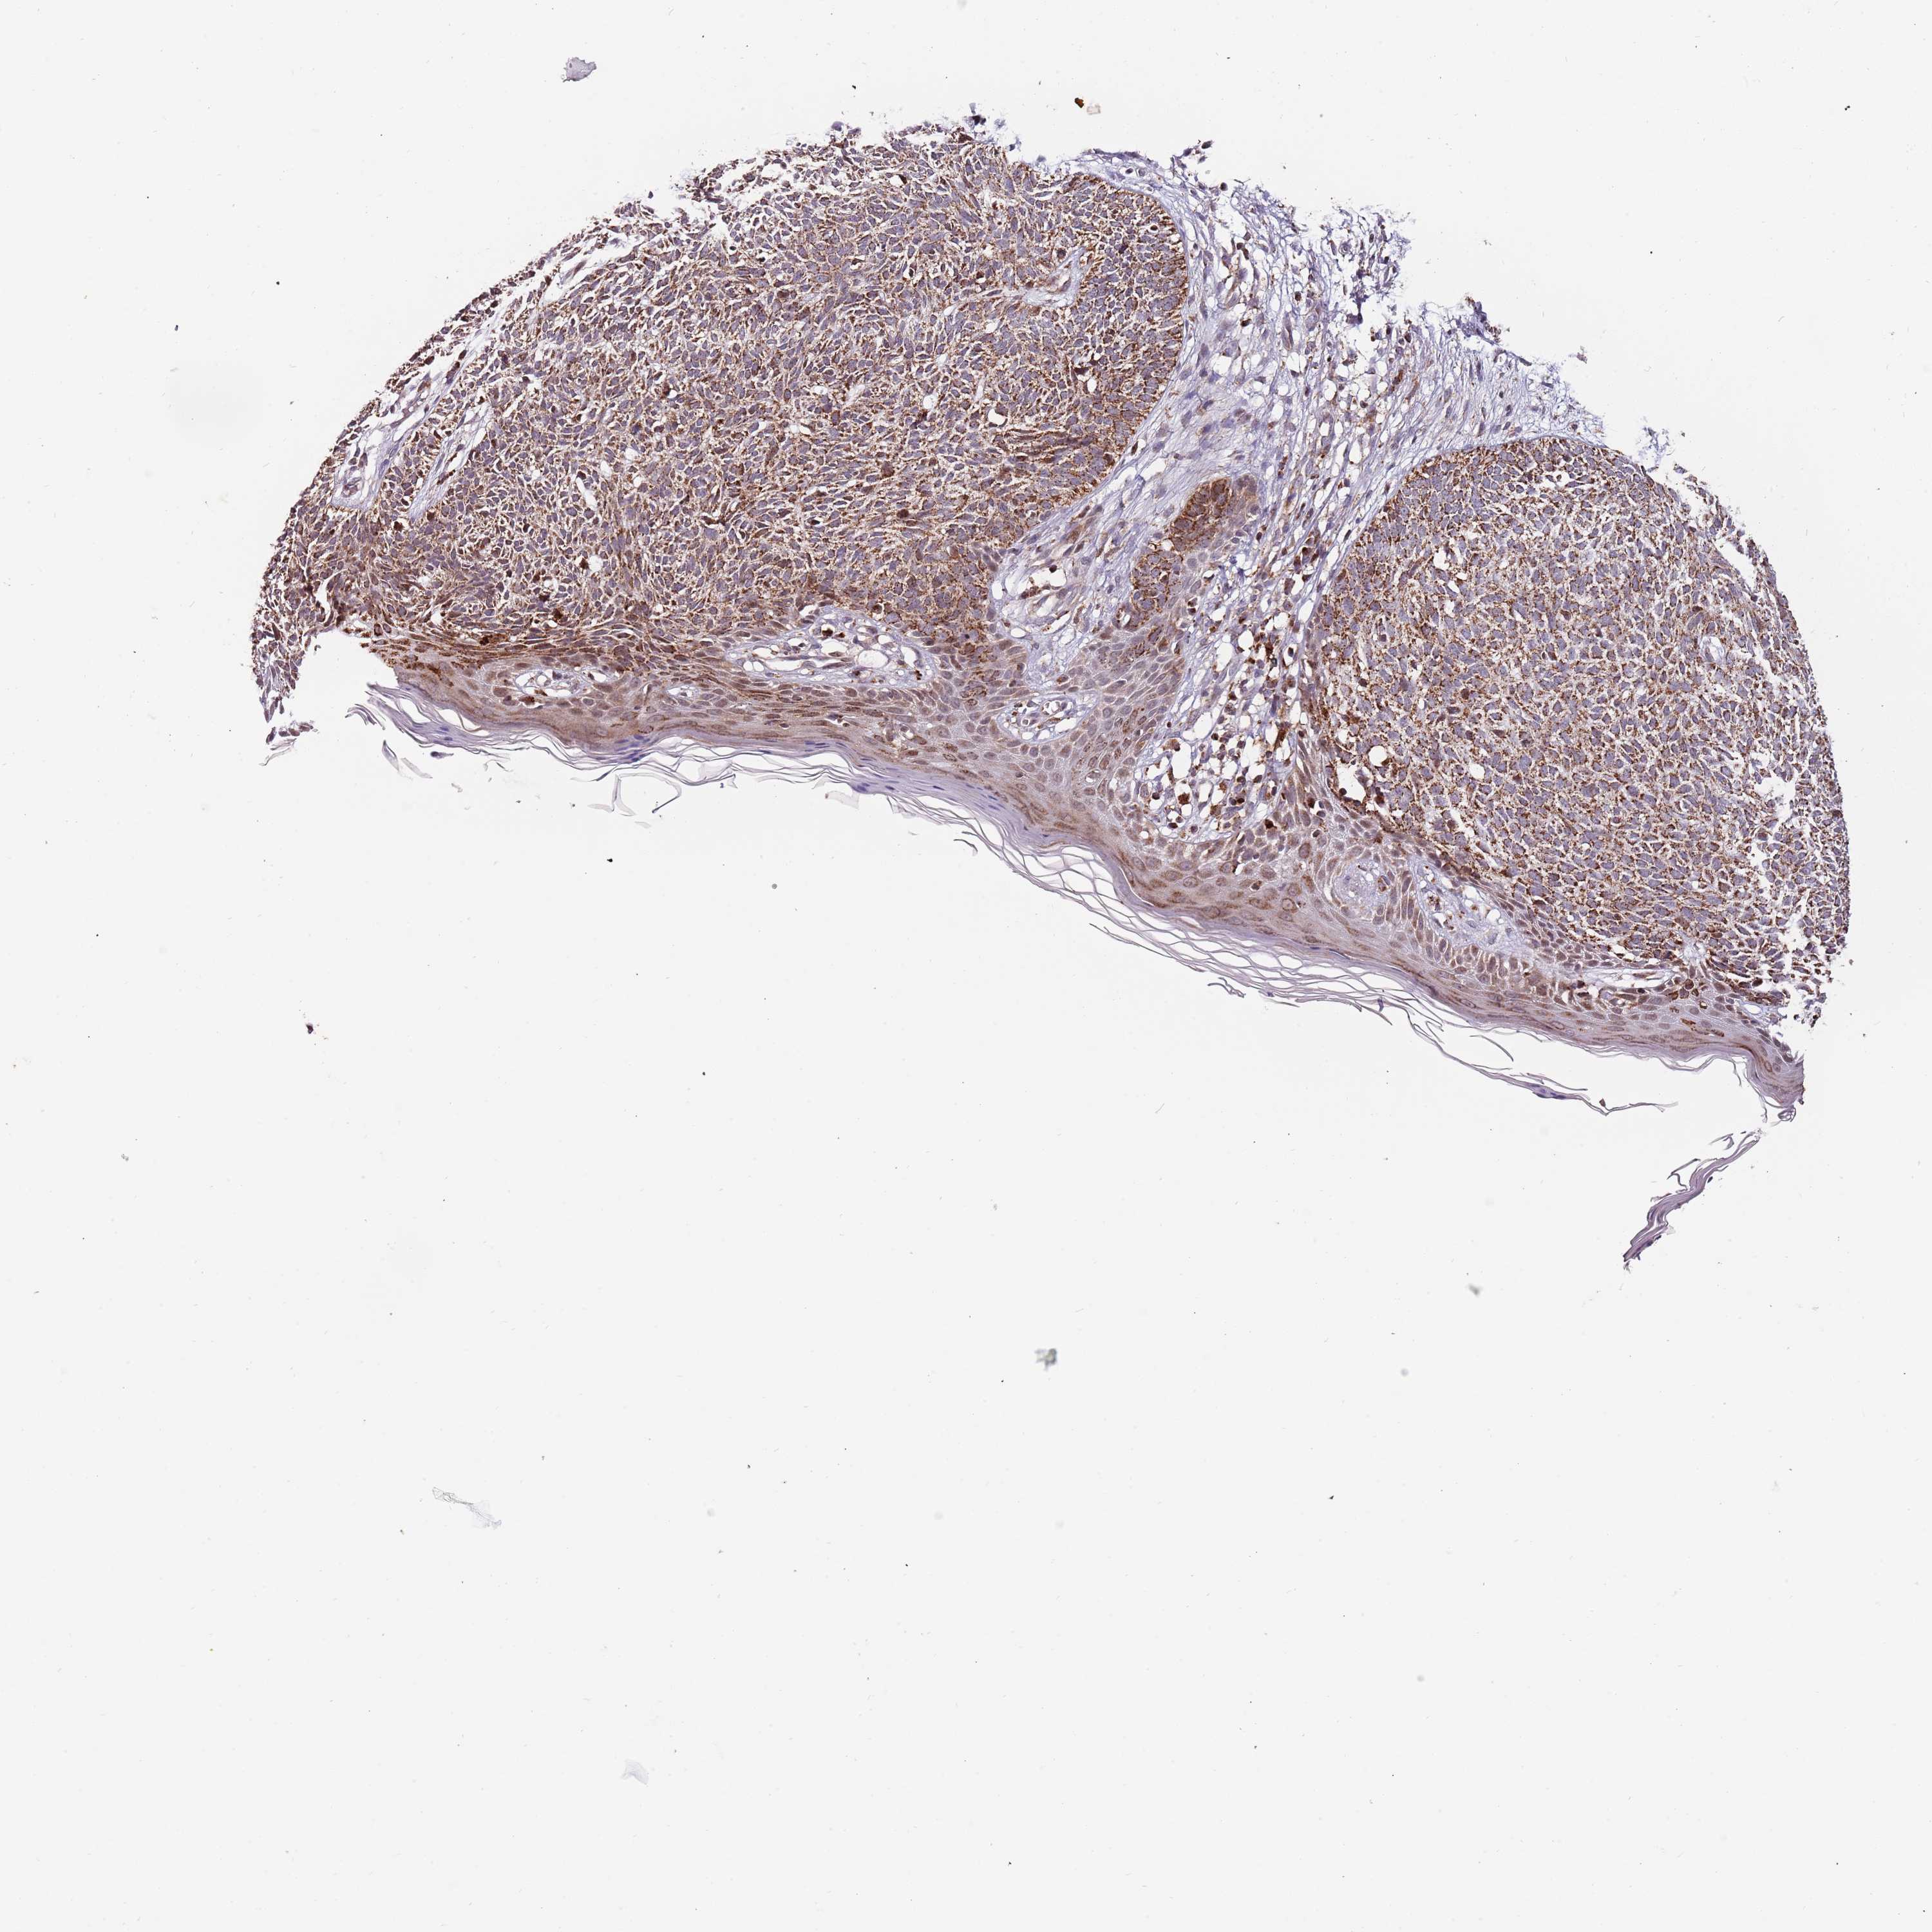

SKIN CANCER - Protein expressioni

A mouse-over function shows sample information and annotation data. Click on an image to view it in a full screen mode. Samples can be filtered based on level of antibody staining by selecting one or several of the following categories: high, medium, low and not detected. The assay and annotation is described here.

Antibody stainingi

Antibody staining in the annotated cell types in the current human tissue is reported as not detected, low, medium, or high, based on conventional immunohistochemistry profiling in selected tissues. This score is based on the combination of the staining intensity and fraction of stained cells.

Each image is clickable and will lead to virtual microscopy that enables deeper exploration of all samples and also displays staining intensity scores, fraction scores and subcellular localization as well as patient and tissue information for each sample.

Antibody HPA040474

Basal cell carcinoma

Squamous cell carcinoma, NOS

Squamous cell carcinoma, metastatic, NOS